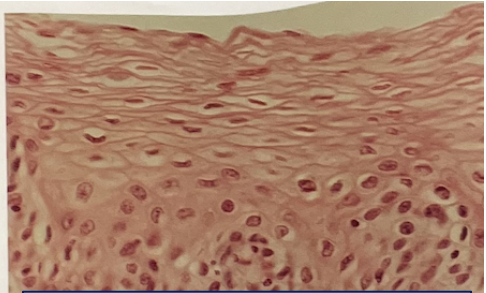

stratified squamous (non-keratinized)